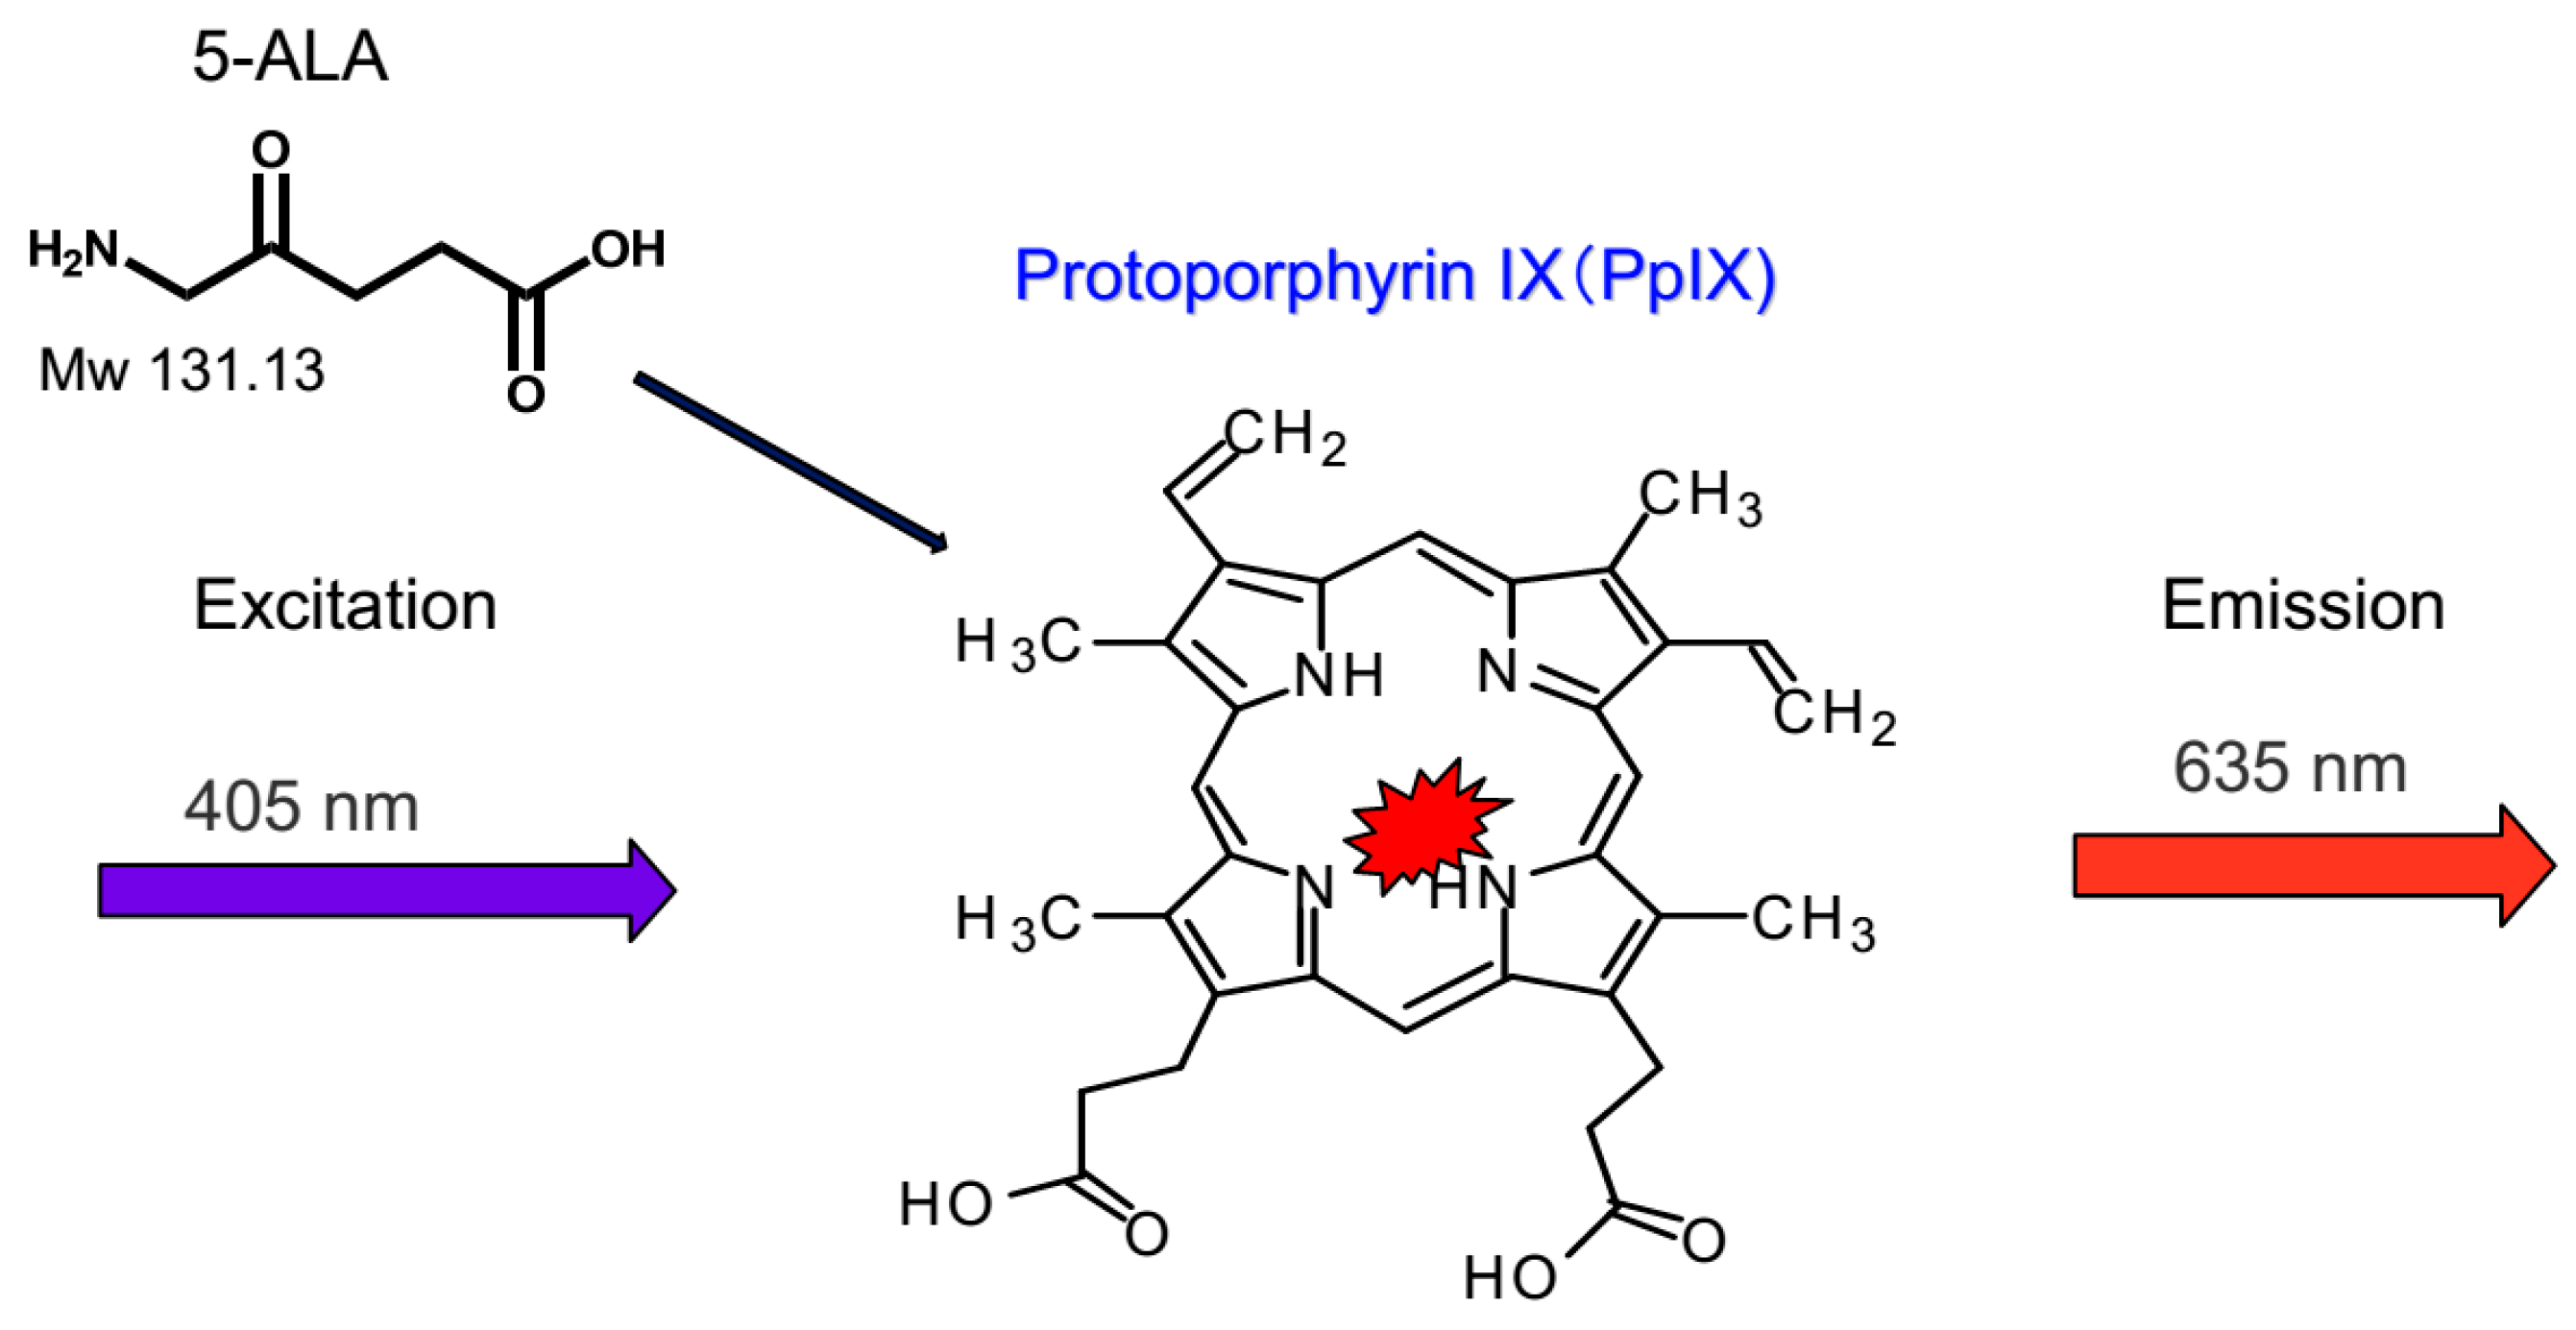

2. Rationale of Photodynamic Diagnosis (PDD) to Detect Peritoneal Metastasis Using 5-Amino-levulinic Acid

3. Molecular Mechanisms of Selective Accumulation of 5-ALA and PpIX in Cancer Cells and Cancer Tissues